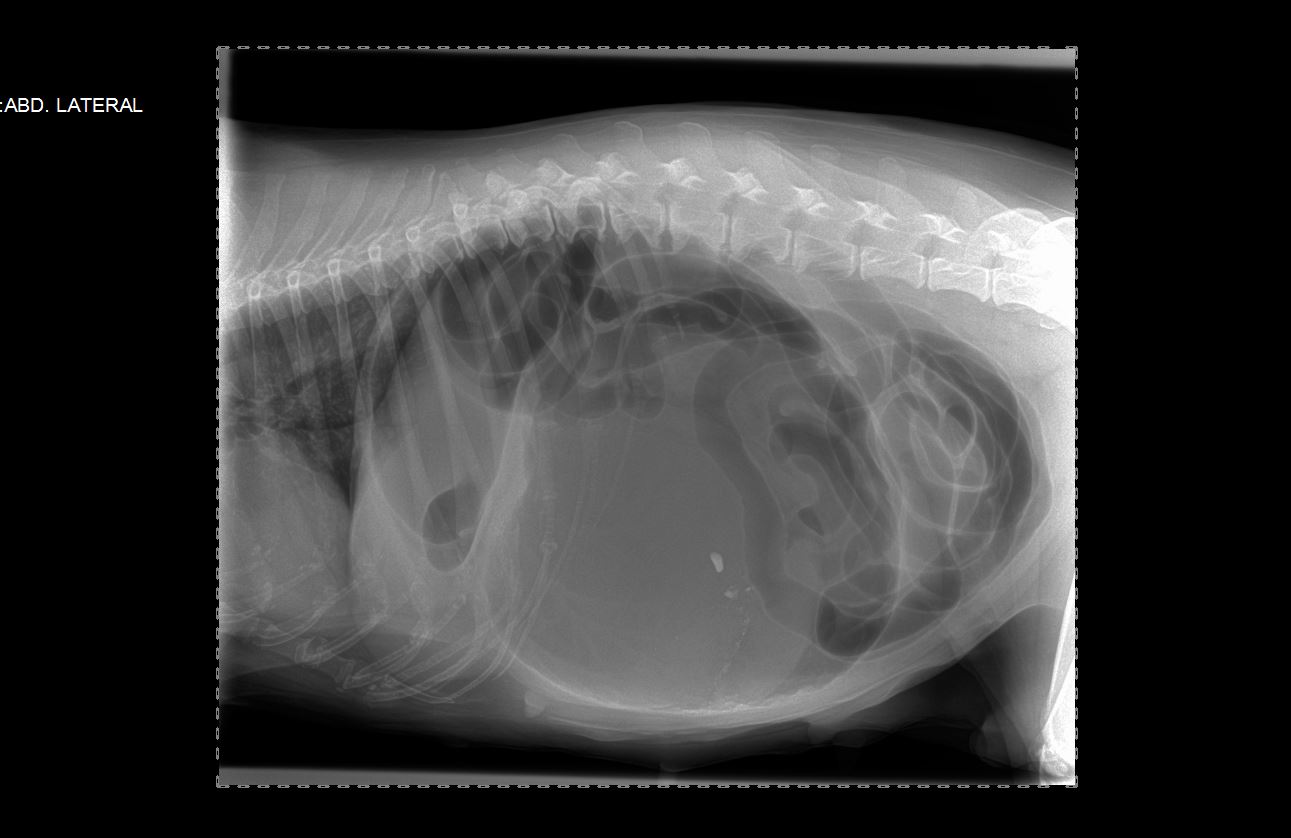

Chirurgies abdominales :

-biopsie d’organes ,

-gastrotomie, entérotomie, entérectomie, gastropexie sdte,

-chirurgie des voies biliaires

-hernie ombilicale, inguinale, diafragmatique perineale

-splenectomie, lobectomie hepathique